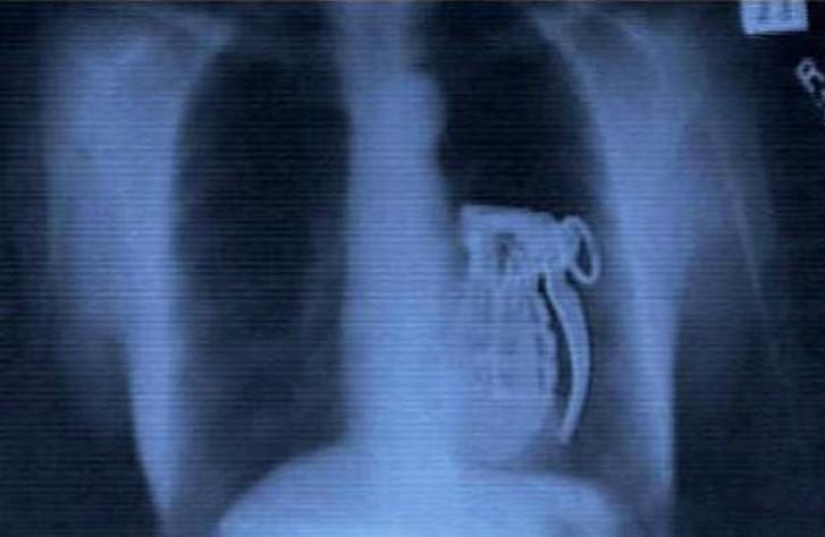

14. Grenade.